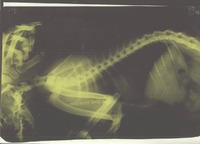

Сделали рентген (результаты прилагаю)

Сегодня сдали анализы на хламидиоз (мазок из глаз), кровь (общий анализ), бак. посев. Анализы будут готовы только во вторник. Сделали еще один рентген. Динамики никакой, заключение : хронический обструктивный бронхит ( сам снимок, заключение и результаты анализов выложу чуть позже ). Рентгенолог сказал, что жидкости нет, но легкие увеличены в объеме.

По снимку: не вижу четкой границы сердца... это мне не видно или снимок низкого качества? Верхушка сердца (низ сердца на снимке) должна касаться грудины. Если этого не происходит, то стоит подозревать быстрее патологию плевры, нежели легких.